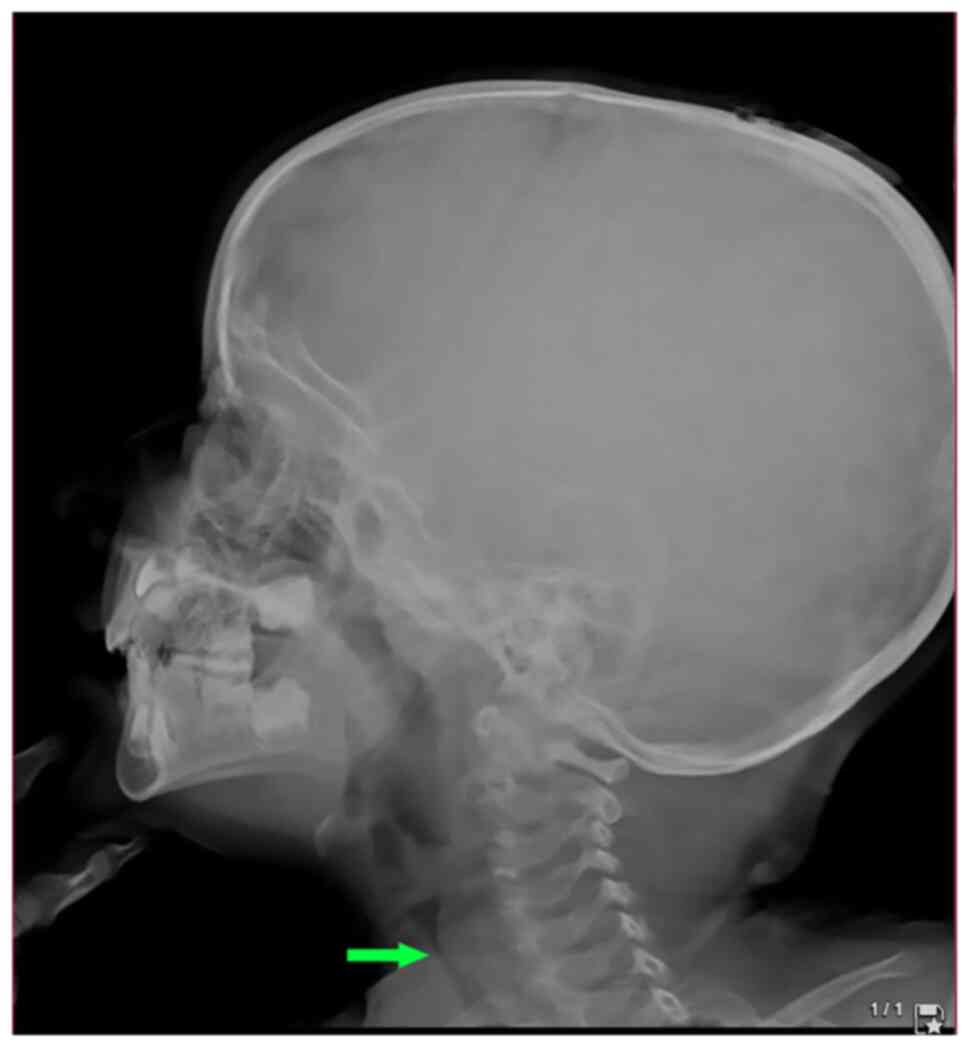

A lateral post-nasal space X-ray was performed, which illustrated tracheal stenosis (Fig. 1). A computed tomography (CT) scan was conducted and confirmed severe subglottic stenosis and a narrowing of the tracheal region just below the vocal cords (Fig. 2).

Figure 1

A pre-tracheostomy lateral post-nasal space radiograph illustrating a bulging from a posterior cervical tracheal wall (arrow) at the level of C5, resulting in severe narrowing of the tracheal air column.